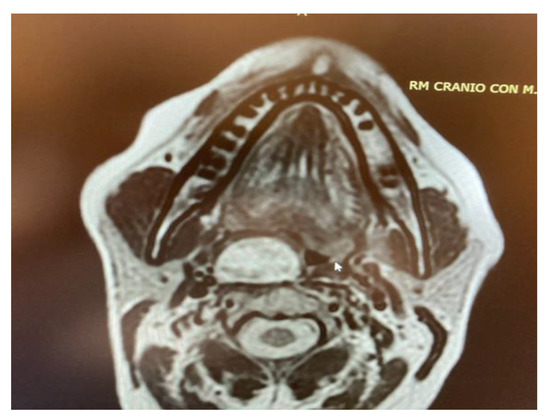

- Two schwannomas (Figure 5) originating from the cervical sympathetic chain and that arose in the superomedial aspect of the PPS, medially to the carotid sheath. The first patient underwent surgery in 2008, the second in 2019. No complications were observed during surgery and no tumour recurrence has been observed after 14 and 4 years, respectively. The only long-term complication observed was Horner syndrome (Figure 6), despite the continuity of the nerve not being interrupted. The hospitalisation time was three days for both patients.